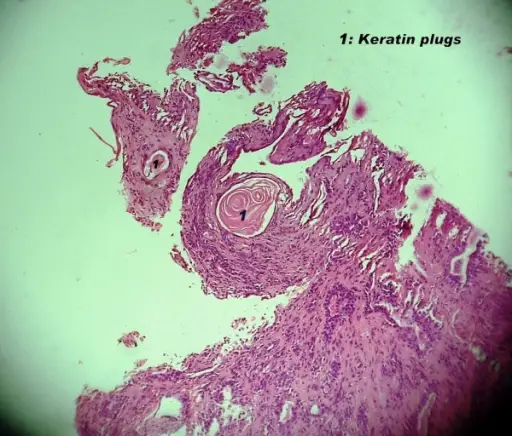

Mucoepidermoid Carcinoma

Mucoepidermoid carcinoma is a malignant tumor made up of squamous and mucin-producing cells.

Mucoepidermoid carcinoma is the most common malignant tumor of the salivary gland.

Mucoepidermoid carcinoma often occurs in the parotid.

The facial nerve is frequently compromised by mucoepidermoid carcinoma.